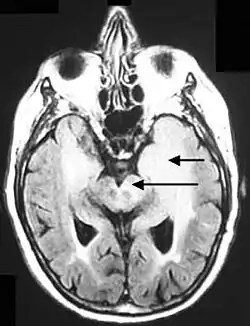

Axial fluid-attenuated inversion recovery MRI image demonstrating tumor-related infiltration involving both temporal lobes (Short arrow), and the substantia nigra (Long arrow).

Axial fluid-attenuated inversion recovery MRI image demonstrating tumor-related infiltration involving both temporal lobes (Short arrow), and the substantia nigra (Long arrow).